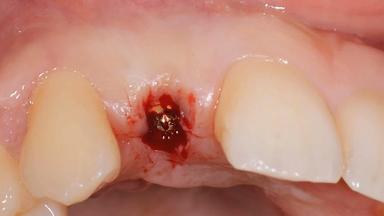

Surgical treatment of a 32-year old, healthy and non-smoking female who required removal and replacement of a lateral maxillary incisor due to internal root resorption. The inflammatory process caused a reduction of the crestal bone level on the distal side of the tooth necessitating an augmentation procedure to meet the patient's high esthetic demands. Due to the high smile line, the thin soft-tissue biotype and triangular-shaped teeth several esthetic risk factors are present.

After flapless tooth removal and a healing period of 6 weeks a diameter-reduced two-piece implant is placed. The bone defect on the facial aspect is corrected with a contour augmentation using autologous bone chips covered with DBBM particles and a collagen membrane according to the Guided Bone Regeneration (GBR) approach.